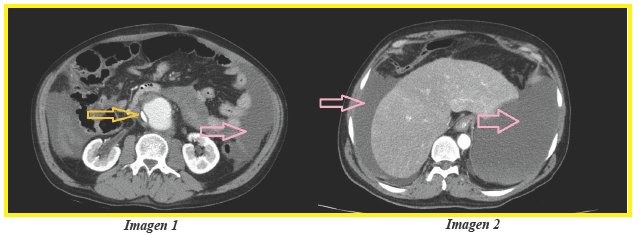

Paciente de sexo masculino de 45 años con antecedente de esquizofrenia en tratamiento con risperidona, acude a urgencias por astenia, dificultad para respirar progresiva de 3 meses de evolución y crecimiento abdominal desde hace 6 meses. Al examen físico se observa abdomen globoso, blando, depresible y sin ningún tipo de dolor a la palpación, se constató anemia severa con hemoglobina 6 gr/dl y resto de laboratorios dentro de parametros normales. Se ingresó al paciente a sala de clínica médica para estudio de la anemia; permaneció en todo momento con signos vitales en rango y a las 24 horas del ingreso se realiza ecografía abdominal donde se constata hidronefrosis derecha, tumoración a nivel de hipogastrio, líquido en cavidad abdominal y se realizó paracentesis diagnóstica con líquido hemático; posteriormente se realizó Tomografía Computarizada con contraste (corte transversal a nivel de T12 y T10 (imagen 1 y 2) respectivamente) y se constató aneurisma disecante de la aorta infrarenal1,2 de 8cm (imagen 1) (flecha naranja) con extravasación de constraste y hemoperitoneo por extravasacion de sangre a cavidad abdominal (imagen 1 y 2) (flecha rosa). Posterior al diagnóstico se realizó cirugía vascular de urgencia, con fallecimiento del paciente durante el procedimiento.

Es llamativo que el cuadro de hemoperitoneo y rotura aneurismática crónica fue inverosímil para el personal médico de urgencias, la evaluación semiológica fue engañosa ya que el paciente no manifestaba ningún tipo de dolor a la palpación abdominal tampoco signos de irritación peritoneal; incluso familiares atribuyeron crecimiento abdominal de 6 meses de evolución a obesidad por ingesta excesiva de alimentos, tránsito intestinal fue normal.

Los medios diagnósticos son indispensables en la medicina moderna, inicialmente se planteó que falta de dolor abdominal se debió a presencia de líquido progresiva en peritoneo que fue tolerando el mismo como el caso de los pacientes con ascitis por causas hepáticas, renales, etc. Se plantearon cantidad de diagnósticos para cuadro de anemia crónica pero el sangrado por pseudoaneurisma roto de aorta abdominal3,4 resultó ser la causa menos probable de anemia.